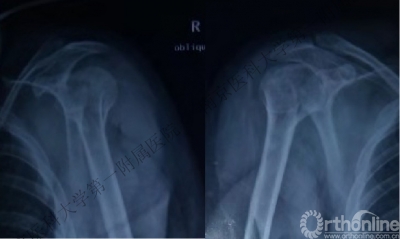

男性,40岁,摔伤后右肩关节肿痛、活动受限2天。

男性,48岁,坠落伤致左肩关节肿痛、活动受限1天。

病例1与病例2是同一类损伤吗?